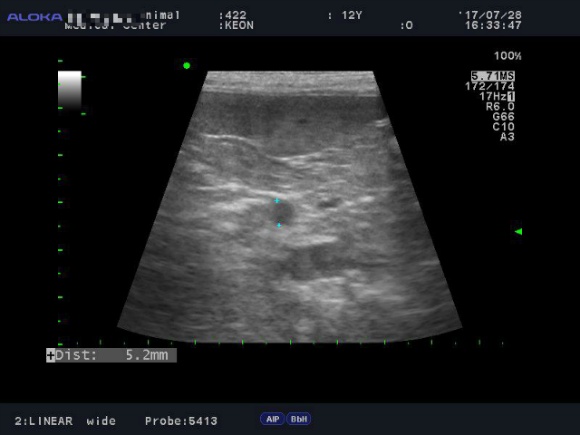

<7월28일> 다시 원점..도로아미타불입니다. 다시봐도 속상하네요 (근데 이게 담낭이 맞긴 한건가..급혼란..)

어제받은 초음파사진들은 몇장 안되니 그냥 다 올려볼게요

(이제와서 뭐가 뭔지도 몰라보는 이 모지란 반려인간..ㅜ)